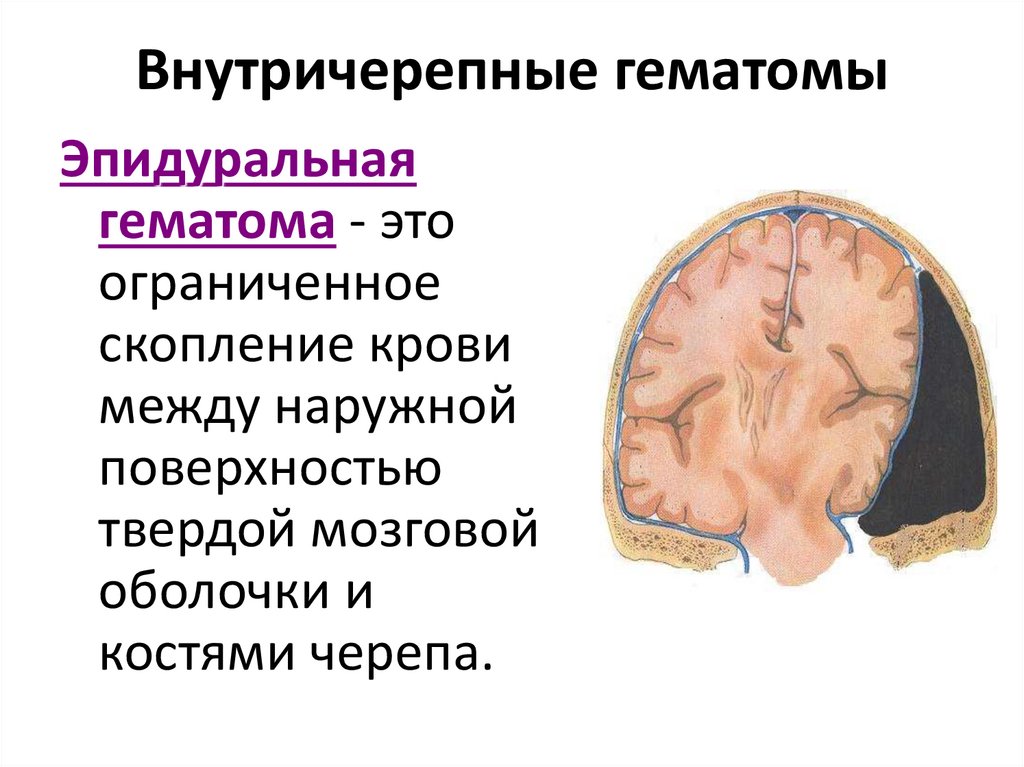

Внутричерепные кровоизлияния у новорожденных презентация - 92 фото